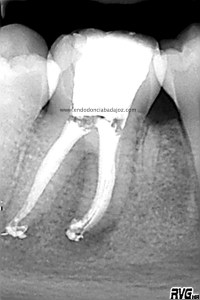

Se trata de un caso similar a este otro visto desde oclusal, observamos un istmo en la raiz mesial que tratamos como si fuesen varios conductos.

Una vez que hemos limpiado los conductos con un sistema de instrumentación  Protaper en combinación con limas K3. Pasamos a obturar los mismos con una técnica de condensación vertical de ola contínua de Buchanan y un backfilling con la gutapercha inyectada de la pistola ObturaII. Tomamos varias proyecciones, orto-mesio-distal

Con estas tres proyecciones nos quedamos mucho más tranquilos y seguros de un buen sellado hermético y tridimensional des sistema de conductos de esta pieza.